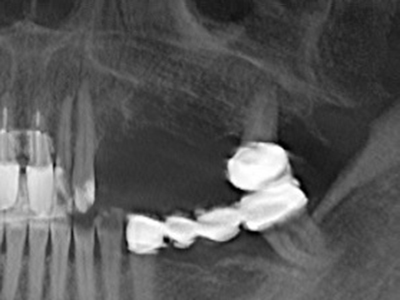

Indication: Preparation near nerves

When surgical procedures are performed on bone in the immediate vicinity of sensitive structures such as blood vessels or nerves, rotary instruments pose a significant risk of iatrogenic injury. Piezoelectric devices can be helpful for preparation of bone covers and removal of hard tissue close to nerves, particularly for exposure of nerves after iatrogenic injury but also during nerve lateralization for resective and reconstructive procedures or implant placement (Fig. 17-20). Light contact between the piezotip and the nerve does not generally result in damage but proceeding incautiously with saw-like motions or attachments where a residual bone substrate remains may cause temporary or even permanent nerve damage. However, the risk of damage is considered to be substantially lower than when using saws or milling instruments (Pereira, Gealh et al. 2014).